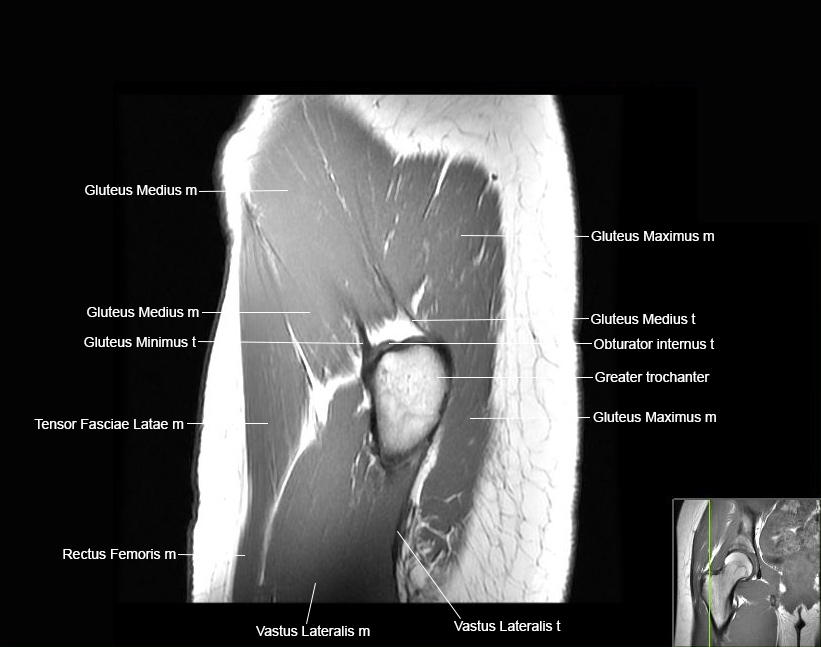

Hip

Basic Hip MRI

MRI Hip Anatomy

Scroll using the mouse wheel or the arrows